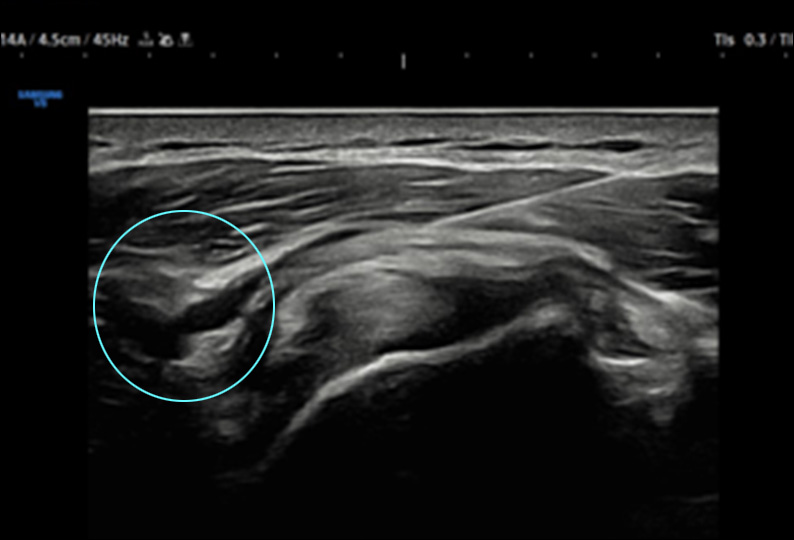

유착성 관절낭염(오십견)과 어깨충돌증후군으로 통증과 관절 움직임 제약이 큰 70대 환자.

초음파 유도 하에 하이펑쳐 시술로 호전

하이펑쳐 주사

조직재생 유도 물질로 잘 알려진 PDRN과

자하거(태반)를 환자별 맞춤 배합하여 초음파를 보며

어깨 통증 병변에 주입